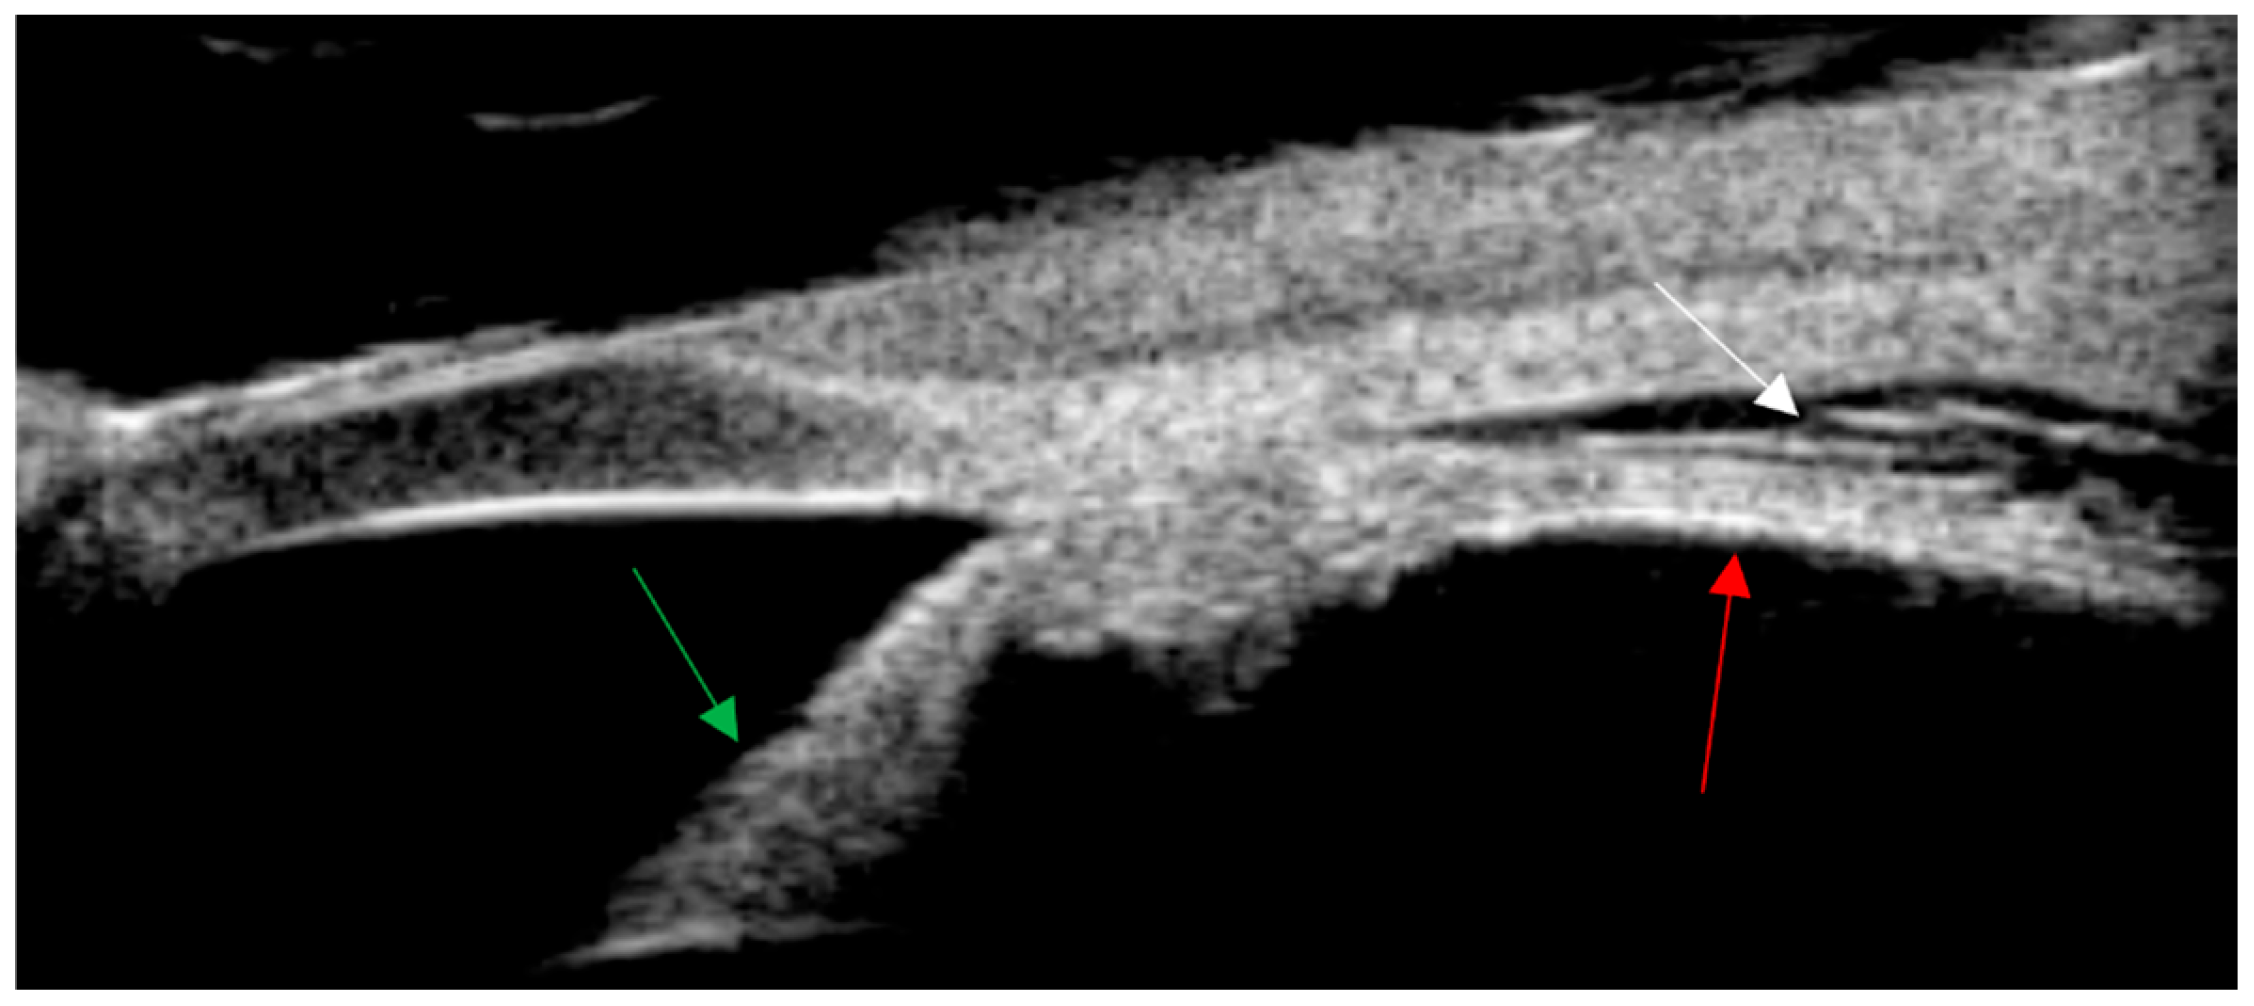

Fundus of a six-year-old Chinese girl with cat scratch disease. At the time of the patient’s visit for examination, the vision of the left eye was light perception, the vision of the right eye was 1.0, the intraocular pressure of the right eye was 17 mmHg, and the intraocular pressure of the left eye was 12 mmHg. There was corneal endothelial cell deposition on the left+, aqueous flare++, dilated pupil, clear lens, vitreous opacity++, total retinal shallow detachment. There was a huge yellow–white mass under the temporal superior retina adjacent to the optic disc. The mass involved the macular area. A month ago, a hard lump was found below the inguinal area on the inner side of her left thigh, accompanied by itching and tenderness. There was no rupture, swelling, fever or cough. Eighteen days ago, there was obvious conjunctival congestion in the left eye. The lump on the left thigh became enlarged and reddened. The skin temperature was high and there was tenderness but no rupture. The local hospital treated it as an infection (the medication was unclear). The parents unintentionally noticed a decrease in vision in the left eye, with only light perception. At the local hospital, ocular B-ultrasound showed an enhanced band-like echo in the dark area of the vitreous body of the left eye. B-ultrasound of the lymph nodes at the root of the left thigh showed enhanced local tissue echo. The white blood cell count was 17.78 × 109/L. Considering infection, cephalosporin injection was given for 11 days without improvement. We immediately took the vitreous humour for the metagenome next-generation sequencing (mNGS), and Bartonella henselae was detected as a result. Moreover, the pathological examination of the thigh nodule puncture showed the typical characteristics of Bartonella infection: the thigh nodule was soft tissue purulent inflammation, with special staining Warthin Starry (+) and Gram staining (-). Since the examination results were clear, no other tests were conducted. The explanation of the arrows: The green arrow indicates the retinal folds caused by retinal detachment, the red arrow indicates the optic disc, and the white arrow indicates the huge yellow–white mass under the retina.